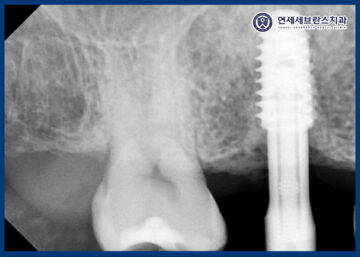

25.07.14 / 25.07.29

<임플란트 제거 후 재식립>

이렇게 일주일 뒤

임플란트의 수치를 측정해보니

매우 낮게 나왔으며,

누를 때 통증을 호소하셔서

제거 후 곡반정동임플란트를

재식립하기로 결정하였습니다.

곡반정동임플란트

25.07.29

<기존 임플란트 확인>

기존 임플란트를 제거하고 확인해 보았을 때,

염증이나 오염이 확인되지 않아,

바로 재식립을 진행하였습니다.

내부의 오염 가능성이 있기 때문에

정밀하게 확인하였는데,

특별한 문제 없이 깨끗하여 별도의 뼈이식 없이

임플란트를 식립하는 과정을 거쳤답니다.